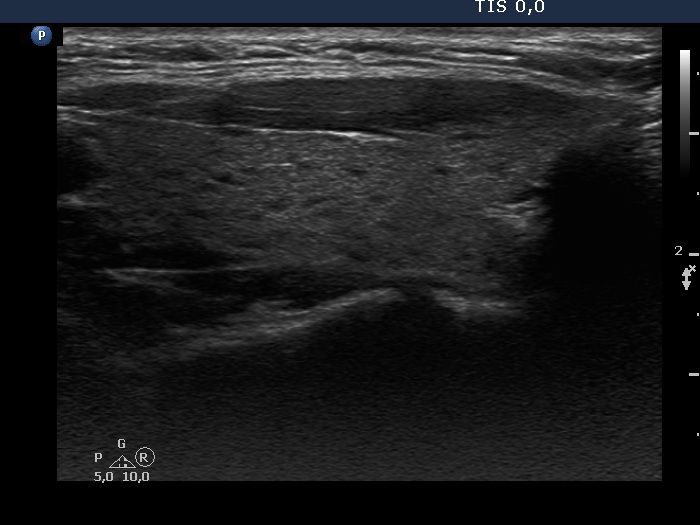

Consecutive patients with the final diagnosis of Hashimoto's thyroiditis - case 31 (1114) (ultrasonographic picture 2)

Right lobe, longitudinal scan

Right lobe, longitudinal scan. The echogenicity index is around 5%.